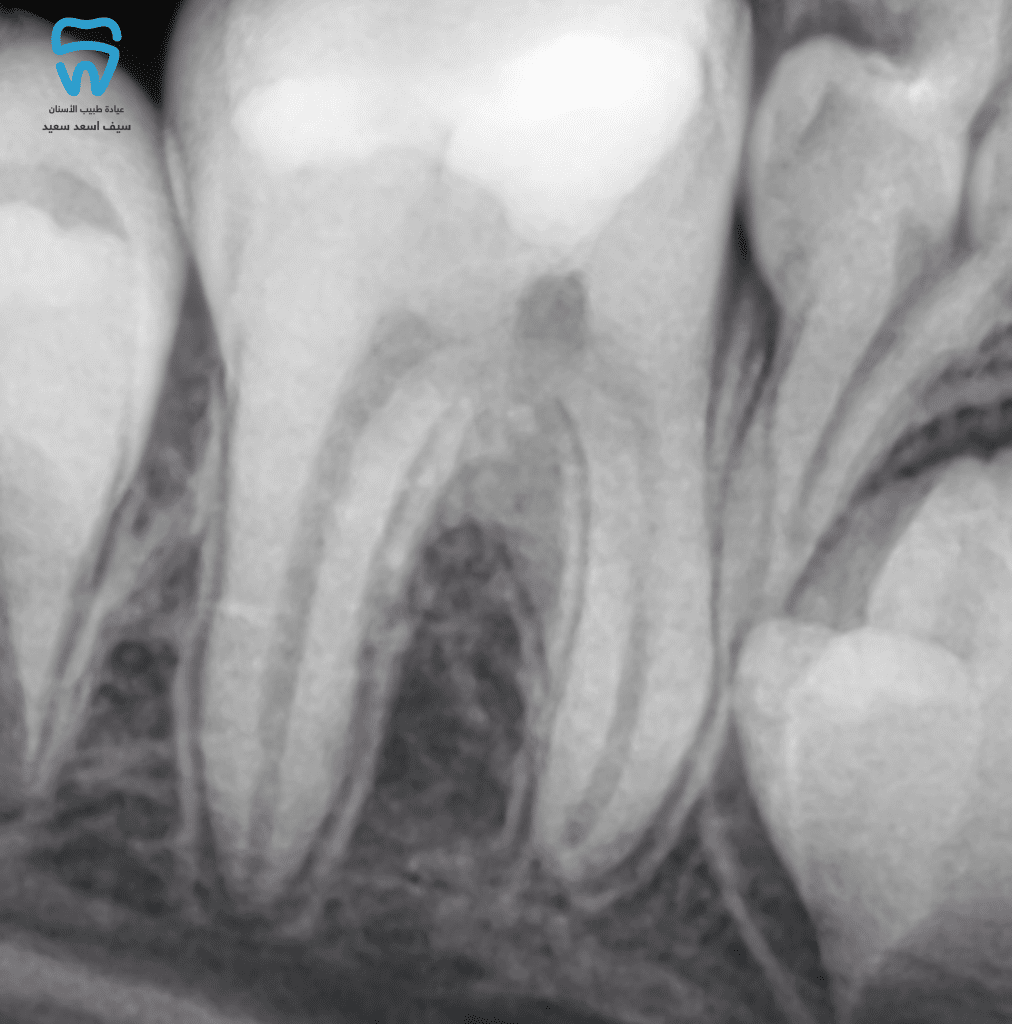

Regarding this clinical scenario, based on the clinical diagnosis, the radiographic findings and the amount of pulp damaged by caries, partial pulpotomy was the chosen treatment depending on the famous study by Cvek in 1978, when he reported that 96% of compromised teeth healed after removal of 2-3 mm of the inflamed pulp. thus, this found the possible solution for open apices, dental trauma, and teeth with developmental defects. [2]

9-year-old female patient presented with pain during eating and discomfort in the lower right permanent molar.

1 year later showing Root end completion

Radiograph showing the tooth 3 years later